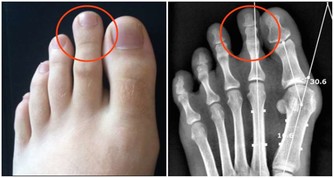

***3.尿量過多或過少***

健康的人每天排尿次數大約為4-6次,尿量約800-2000毫升,平均為1500毫升。如果排尿次數和尿量過多或過少,都可能是腎髒病的表現,特別是夜間多尿往往是腎髒病的信號。